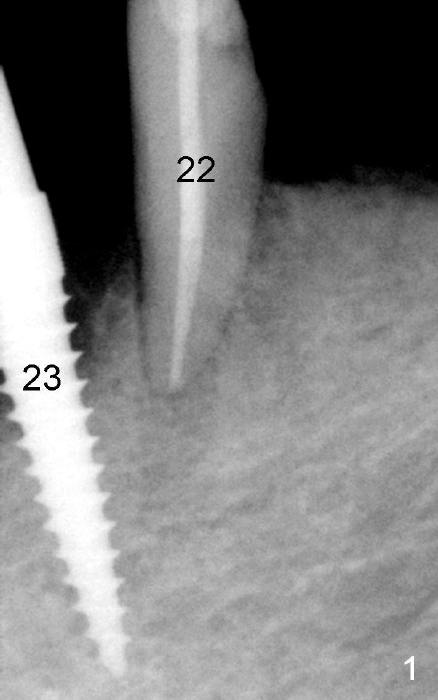

A 73-year-old lady has an existing upper complete denture and a lower flipper. A few days after #23 exfoliation, a 3.5x17 mm one piece implant is placed (Fig.1) and an immediate provisional is fabricated. Later the lower flipper is remade. The one piece implant and the provisional have been doing well for 7 months by the time Fig.2 is taken.